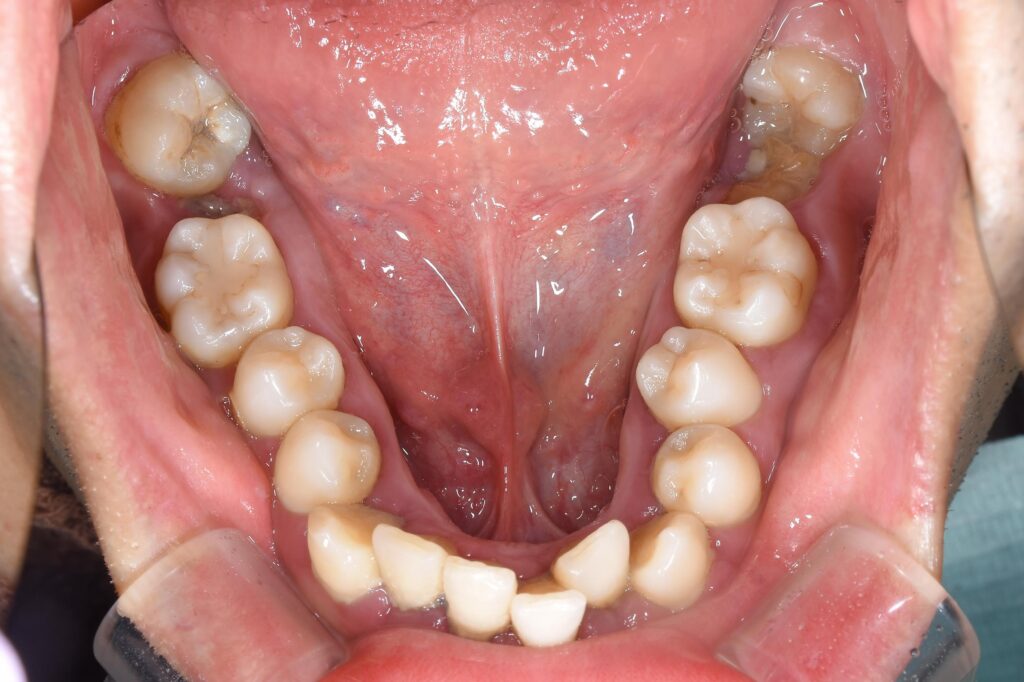

まずは初診時の状態です。

【初診時】

初診時、歯周病・虫歯も進行しており、まずは初期治療として歯周病治療・虫歯治療を行いました。

③歯並びに関して、問題点は歯列弓の狭窄を認め、歯がガタガタになってしまっています。また、上顎の歯が突出してしまい、出っ歯になっています。